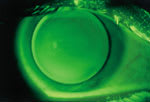

An apical alignment fluorescein pattern |

A well centered RGP lens |